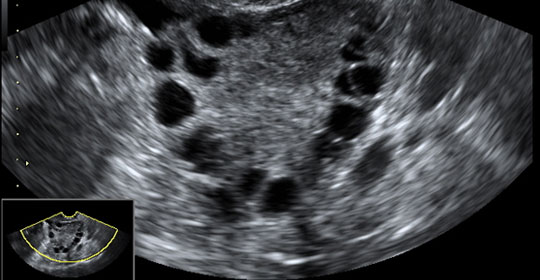

Síndrome de Ovarios Poliquísticos

¿Qué es el síndrome de ovarios poliquísticos? El síndrome de ovarios poliquisticos es un trastorno que afecta hasta un 5-10% de las mujeres, y tiene 3 características principales: niveles